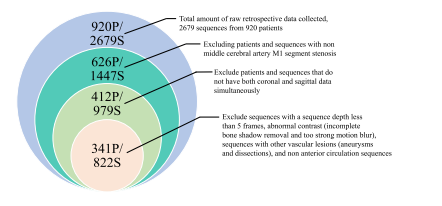

DSA images serve as the gold standard in MT procedures, necessitating the utilization of dual views—coronal and sagittal—to ascertainthe mTICI score accurately. Relying solely on one view may obscurecertain vessels and lead to imprecise scoring. Currently, the absenceof a publicly available mTICI scoring dataset based on dual-view DSAsequences impedes the progress of automatic mTICI scoring research.To contribute to this field and provide a benchmark for systematicmethod comparisons, under the supervision of physicians, we havecompiled and publicly released a self-labeled dual-view DSA imagedataset for automatic mTICI scoring. We named this dataset AutomaticmTICI Scoring (AmTICIS). To the best of our knowledge, this is the firstpublicly available mTICI scoring dataset. The ethical committee at thecooperative hospital authorized the disclosure of all data in this study,conducted in strict accordance with the World Medical Association Declaration of Helsinki Ethical Principles for Medical Research InvolvingHuman Subjects.

3.1 材料 数字减影血管造影(DSA)图像是机械取栓术(MT)中的金标准,需要利用冠状位和矢状位这两个视图来准确确定改良脑梗死溶栓分级(mTICI)评分。仅依靠一个视图可能会使某些血管难以看清,从而导致评分不准确。 目前,缺乏基于双视图DSA序列的公开可用的mTICI评分数据集,这阻碍了自动mTICI评分研究的进展。为了对该领域做出贡献,并为系统的方法比较提供一个基准,在医生的指导下,我们整理并公开发布了一个自行标注的用于自动mTICI评分的双视图DSA图像数据集。我们将这个数据集命名为自动mTICI评分(AmTICIS)数据集。据我们所知,这是第一个公开可用的mTICI评分数据集。 合作医院的伦理委员会批准了本研究中所有数据的公开披露,本研究严格按照世界医学协会《赫尔辛基宣言——涉及人类受试者医学研究的伦理原则》进行。

Fig. 2. The entry and exit criteria for DSA data, P represents the patient, and S denotesthe sequence.

图2:数字减影血管造影(DSA)数据的纳入和排除标准,P代表患者,S表示序列。